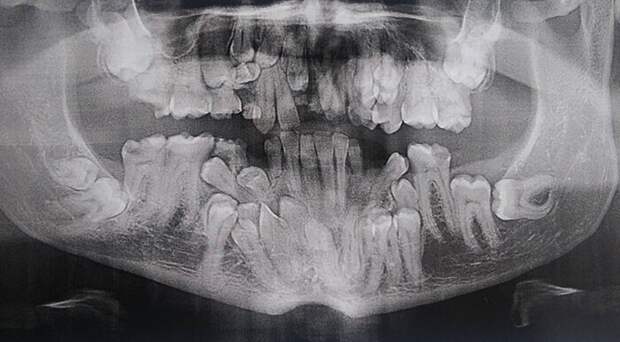

«У меня клейдокраниальный дизостоз, или, если проще, у меня в челюсти много лишних «запасных» зубов»

«Я дантист, но рентгеновские снимки детей 6-12 лет меня немного пугают до сих пор»